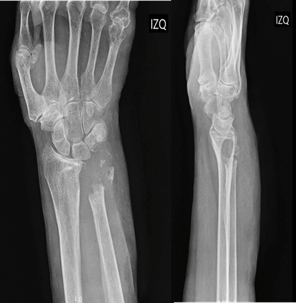

Posteriormente, consultó en el servicio de urgencias del hospital Carlos Van Buren de Valparaíso por exacerbación del dolor, constatándose aumento de volumen de muñeca y antebrazo izquierdo (Figura 1), razón por la que se le realizó una radiografía que evidenció lesiones líticas a nivel de epífisis distal del cúbito y parte del radio (Figura 2). Se sospechó un tumor óseo, por lo que se decidió hospitalizarla para complementar el estudio con una tomografía computada (TAC) de la muñeca, que confirmó los hallazgos radiológicos (Figura 3). Además, se le realizó un TAC de tórax, abdomen y pelvis, que evidenció adenopatías axilares izquierdas de aspecto secundario, sin otras lesiones sugerentes de metástasis o lesión sospechosa neoplásica primaria. Se solicitó un cintigrama óseo que evidenció aumento de la actividad osteoclástica intensa en el extremo distal del cúbito y radio izquierdo.

Figura 2 Radiografía de muñeca izquierda, proyecciones anteroposterior y lateral. Se evidencia lesiones osteolíticas del extremo distal del cúbito y parte distal del radio.